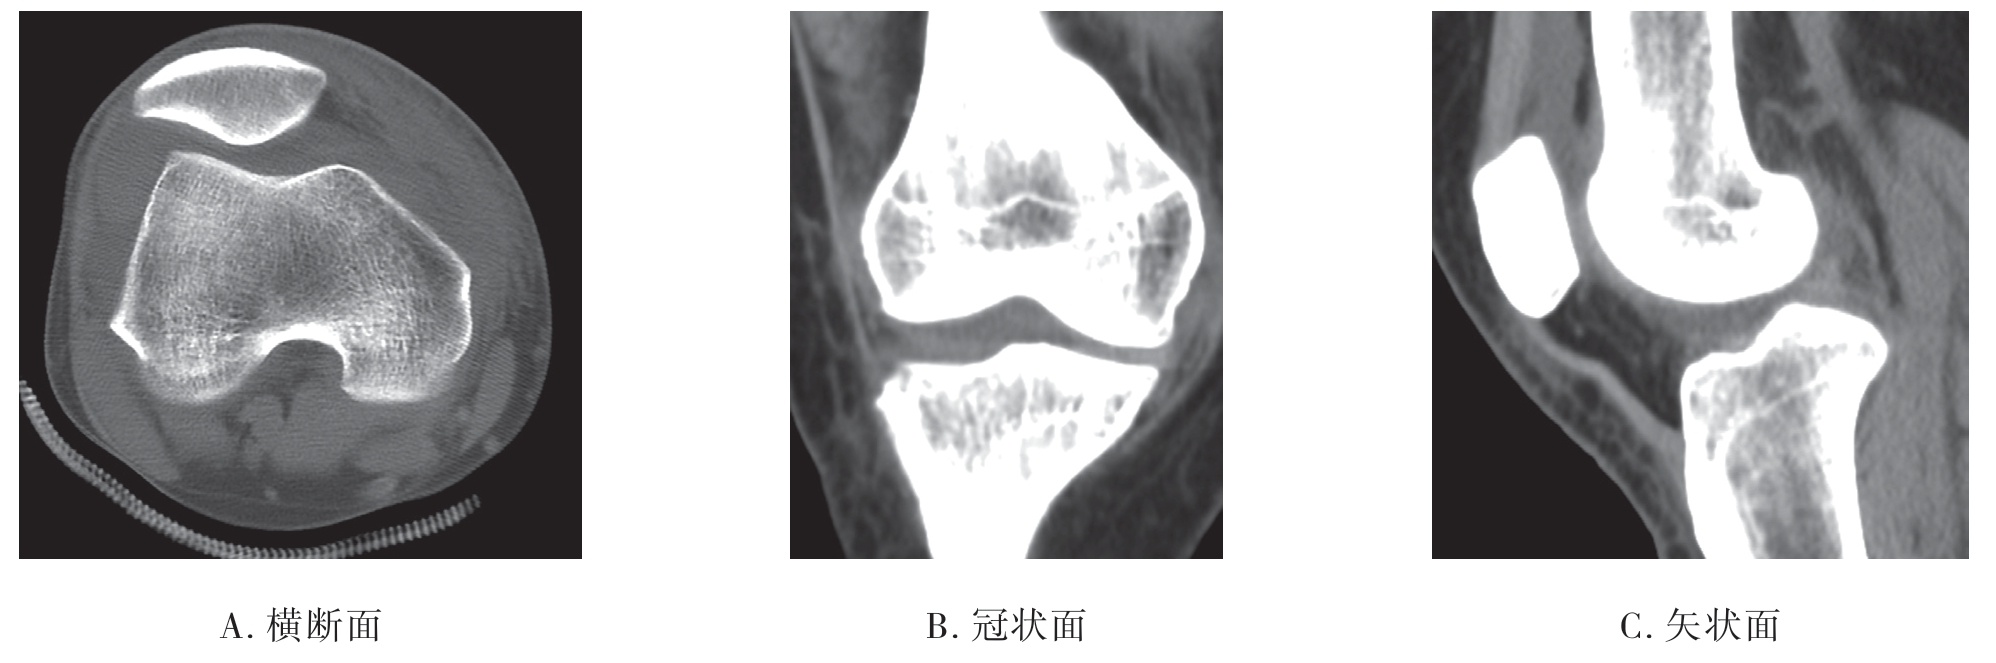

1.CT平扫图像的识别 CT平扫首先是有多幅横断图像,其次是骨皮质呈高密度的白影,而肌肉、肌腱等软组织则呈中等密度的灰影,脂肪组织则表现为较低密度的灰黑影(图7-1-2)。

图7-1-2 膝关节CT平扫